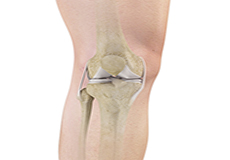

Total Knee Replacement

A Total Knee Replacement (TKR) or Total Knee Arthroplasty is a surgery that replaces an arthritic knee joint with artificial metal or plastic replacement parts called the 'prostheses'.